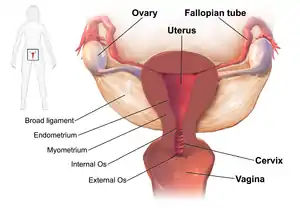

| Drawing showing the usual sites of infection in pelvic inflammatory disease | |

Pelvic inflammatory disease, also known as pelvic inflammatory disorder (PID), is an infection of the upper part of the female reproductive system, namely the uterus, fallopian tubes, and ovaries, and inside of the pelvis.[5][2] Often, there may be no symptoms.[1] Signs and symptoms, when present, may include lower abdominal pain, vaginal discharge, fever, burning with urination, pain with sex, bleeding after sex, or irregular menstruation.[1] Untreated PID can result in long-term complications including infertility, ectopic pregnancy, chronic pelvic pain, and cancer.[2][3][4]

The anatomical structure of the internal organs and tissues of the female reproductive tract provides a pathway for pathogens to ascend from the vagina to the pelvic cavity thorough the infundibulum. The disturbance of the naturally occurring vaginal microbiota associated with bacterial vaginosis increases the risk of PID.[17]